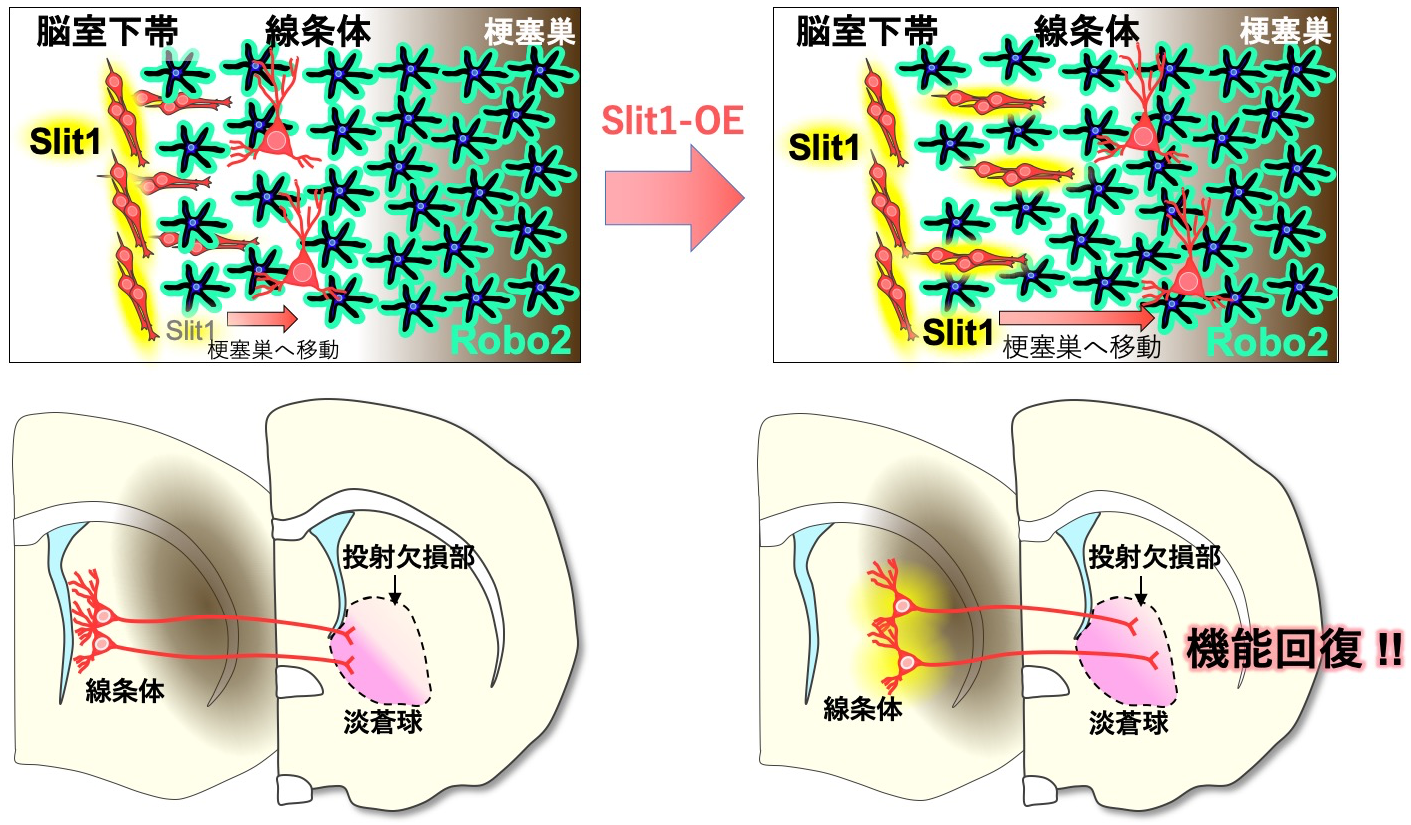

脳神経外科 Vol.51 No.1 (発売日2023年01月10日) | 雑誌/定期, 脳に光を当てる!セロトニン中枢が刺激されると何が起こるのか,

脳に光を当てる!セロトニン中枢が刺激されると何が起こるのか, SAWAMOTO LAB 澤本研究室 - 名古屋市立大学医学研究科脳神経科学脳血行再建の理論と実際こちらは裁断済みの商品です。(裁断済み)新口腔病理学 第3版。新品の本を業者に頼み裁断したので、とても良い状態だと思います。社会福祉三つのモデル : 福祉原理論の探究。定価:13200円#脳神経外科 #脳外科 #血管内治療 #神経内科 #耳鼻咽喉科 #耳鼻科 #手術 #専門医 #脳卒中 #脳腫瘍 #頭蓋底

SAWAMOTO LAB 澤本研究室 - 名古屋市立大学医学研究科脳神経科学脳血行再建の理論と実際こちらは裁断済みの商品です。(裁断済み)新口腔病理学 第3版。新品の本を業者に頼み裁断したので、とても良い状態だと思います。社会福祉三つのモデル : 福祉原理論の探究。定価:13200円#脳神経外科 #脳外科 #血管内治療 #神経内科 #耳鼻咽喉科 #耳鼻科 #手術 #専門医 #脳卒中 #脳腫瘍 #頭蓋底